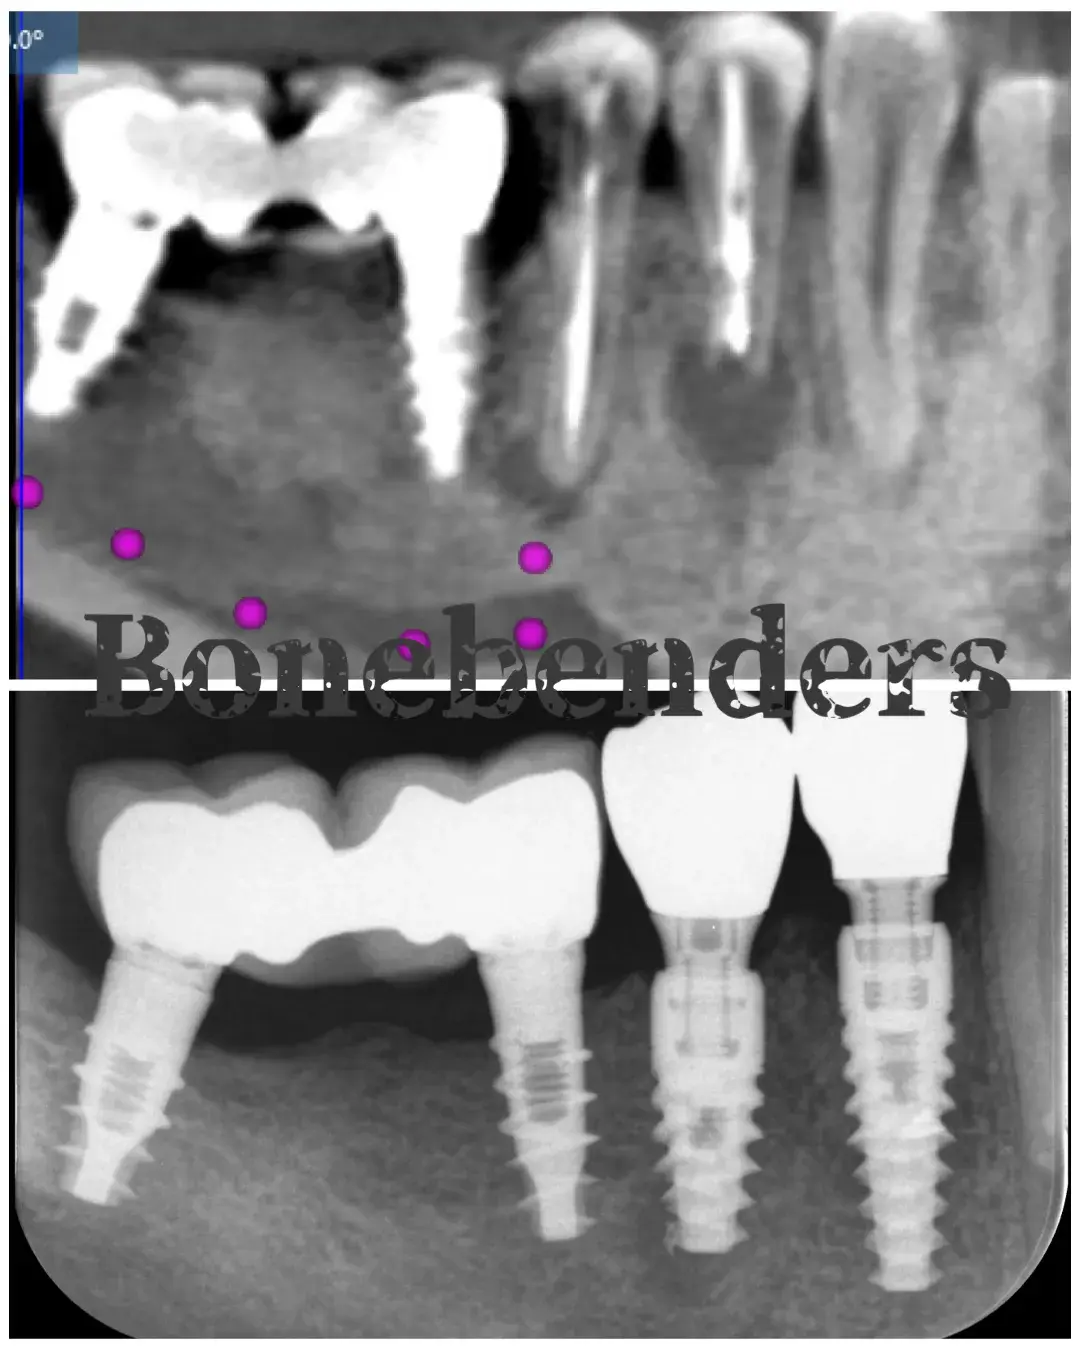

Caso clinico: espansione crestale ERE con impianto immediato e rigenerazione simultanea. Da ponte fallito a impianto in un'unica seduta.

Caso clinico LMSF graftless: due impianti a 1.6/1.5 con espansori a vite calibrati. Gestione localizzata del seno mascellare, senza innesto.

Caso clinico di carico immediato su rialzo crestale del seno mascellare con espansori. Espansione apicale, stabilità >50 Ncm, provvisorio immediato e co...